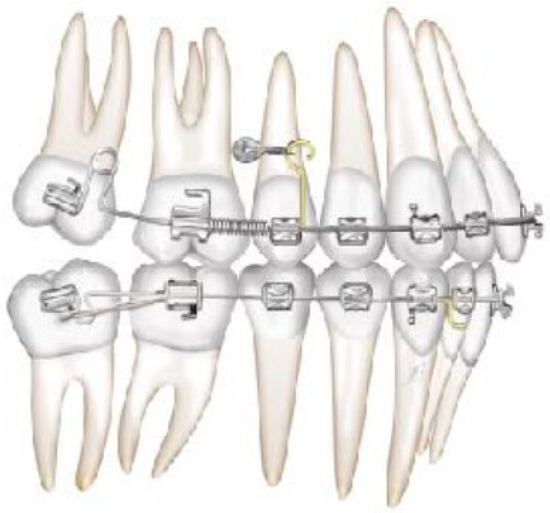

Figure 4. Molar and premolar distalization strategy.

Figure 6. Molar and premolar distalization strategy: Hooks are placed between the laterals and the cuspids. Third-class elastics (1/4” 6 0z) are placed from the tads to the hooks.

Figure 9. Canine and incisor distalization strategy: The cantilevers produce intrusion of the incisors and torque control during retraction.

Figure 10. Canine and incisor distalization strategy.

After achieving the full bonding on the upper arch, two miniscrews (tads) are placed between the upper first molars and the second bicuspid, bilaterally. A 0.19 × 0.25 SS wire is shaped, adding a helical bulbous loop, bent lingually, flush to the second molar tube. At the same time, an active 7° lingual crown torque is placed on the second molar. A long spur with a mesial hook, just mesial to the bracket of the second bicuspid, is soldered. A metallic ligature is placed between the tads and the spurs.

The helical bulbous loop produces space distally to the upper first molars. An open coil is added between the second bicuspid and the first molar in order to move to the distal second and first molar at the same time (Figure 4 and Figure 5). Eventually, an elastic module is placed between the hooks on the second molars and the first molars in order to finish the combined distalization of the upper first molars.

After tad positioning, sequential bonding is applied on the lower arch. An 18 × 0.25 SS arch is shaped, adding a maximum 10° distal tip to the second molar. Hooks are placed between the laterals and cuspids. Third-class elastics (1/4” 6 0z) are placed from the tads to the hooks (Figure 6). The distal tip on the lower second molars will produce a gain of space between molars, with the space needed for the management of the spee curve and the recovery of IMPA.

In this case, right after the spontaneous eruption, a power chain from the right tad was used to derotate and distalize the right upper canine (Figure 8). On the upper arch, a 0.20 × 0.25 SS wire was prepared with modified “cactus-shaped” closing loops, with the aim to close the space between the canines and the laterals. The cactus loop has a double aim. First of all, it is used as a closing loop; activation is produced by tying the loop through a metallic ligature from the tads. Secondly, it serves as a hook for cantilevers. The cantilevers are made using 0.19 × 0.25 TMA. The retraction of the upper incisors is supported by two cantilevers applied distally on the tads. The cantilevers will support the mechanics in order to produce intrusion of the incisors and torque control during retraction [1] (Figure 9 and Figure 10).